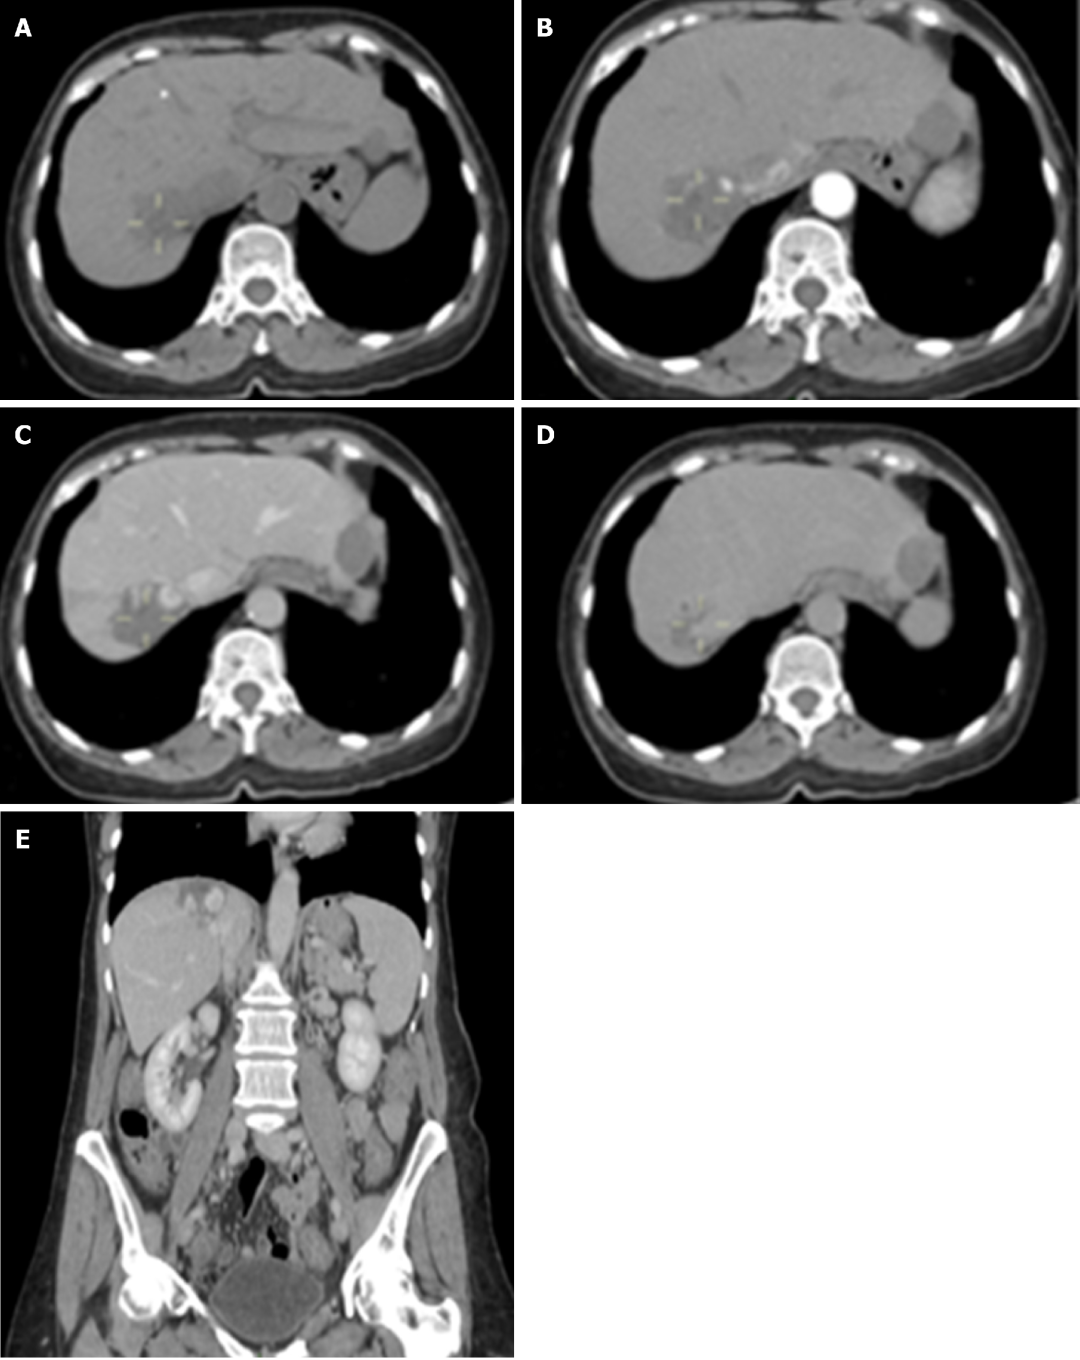

图2